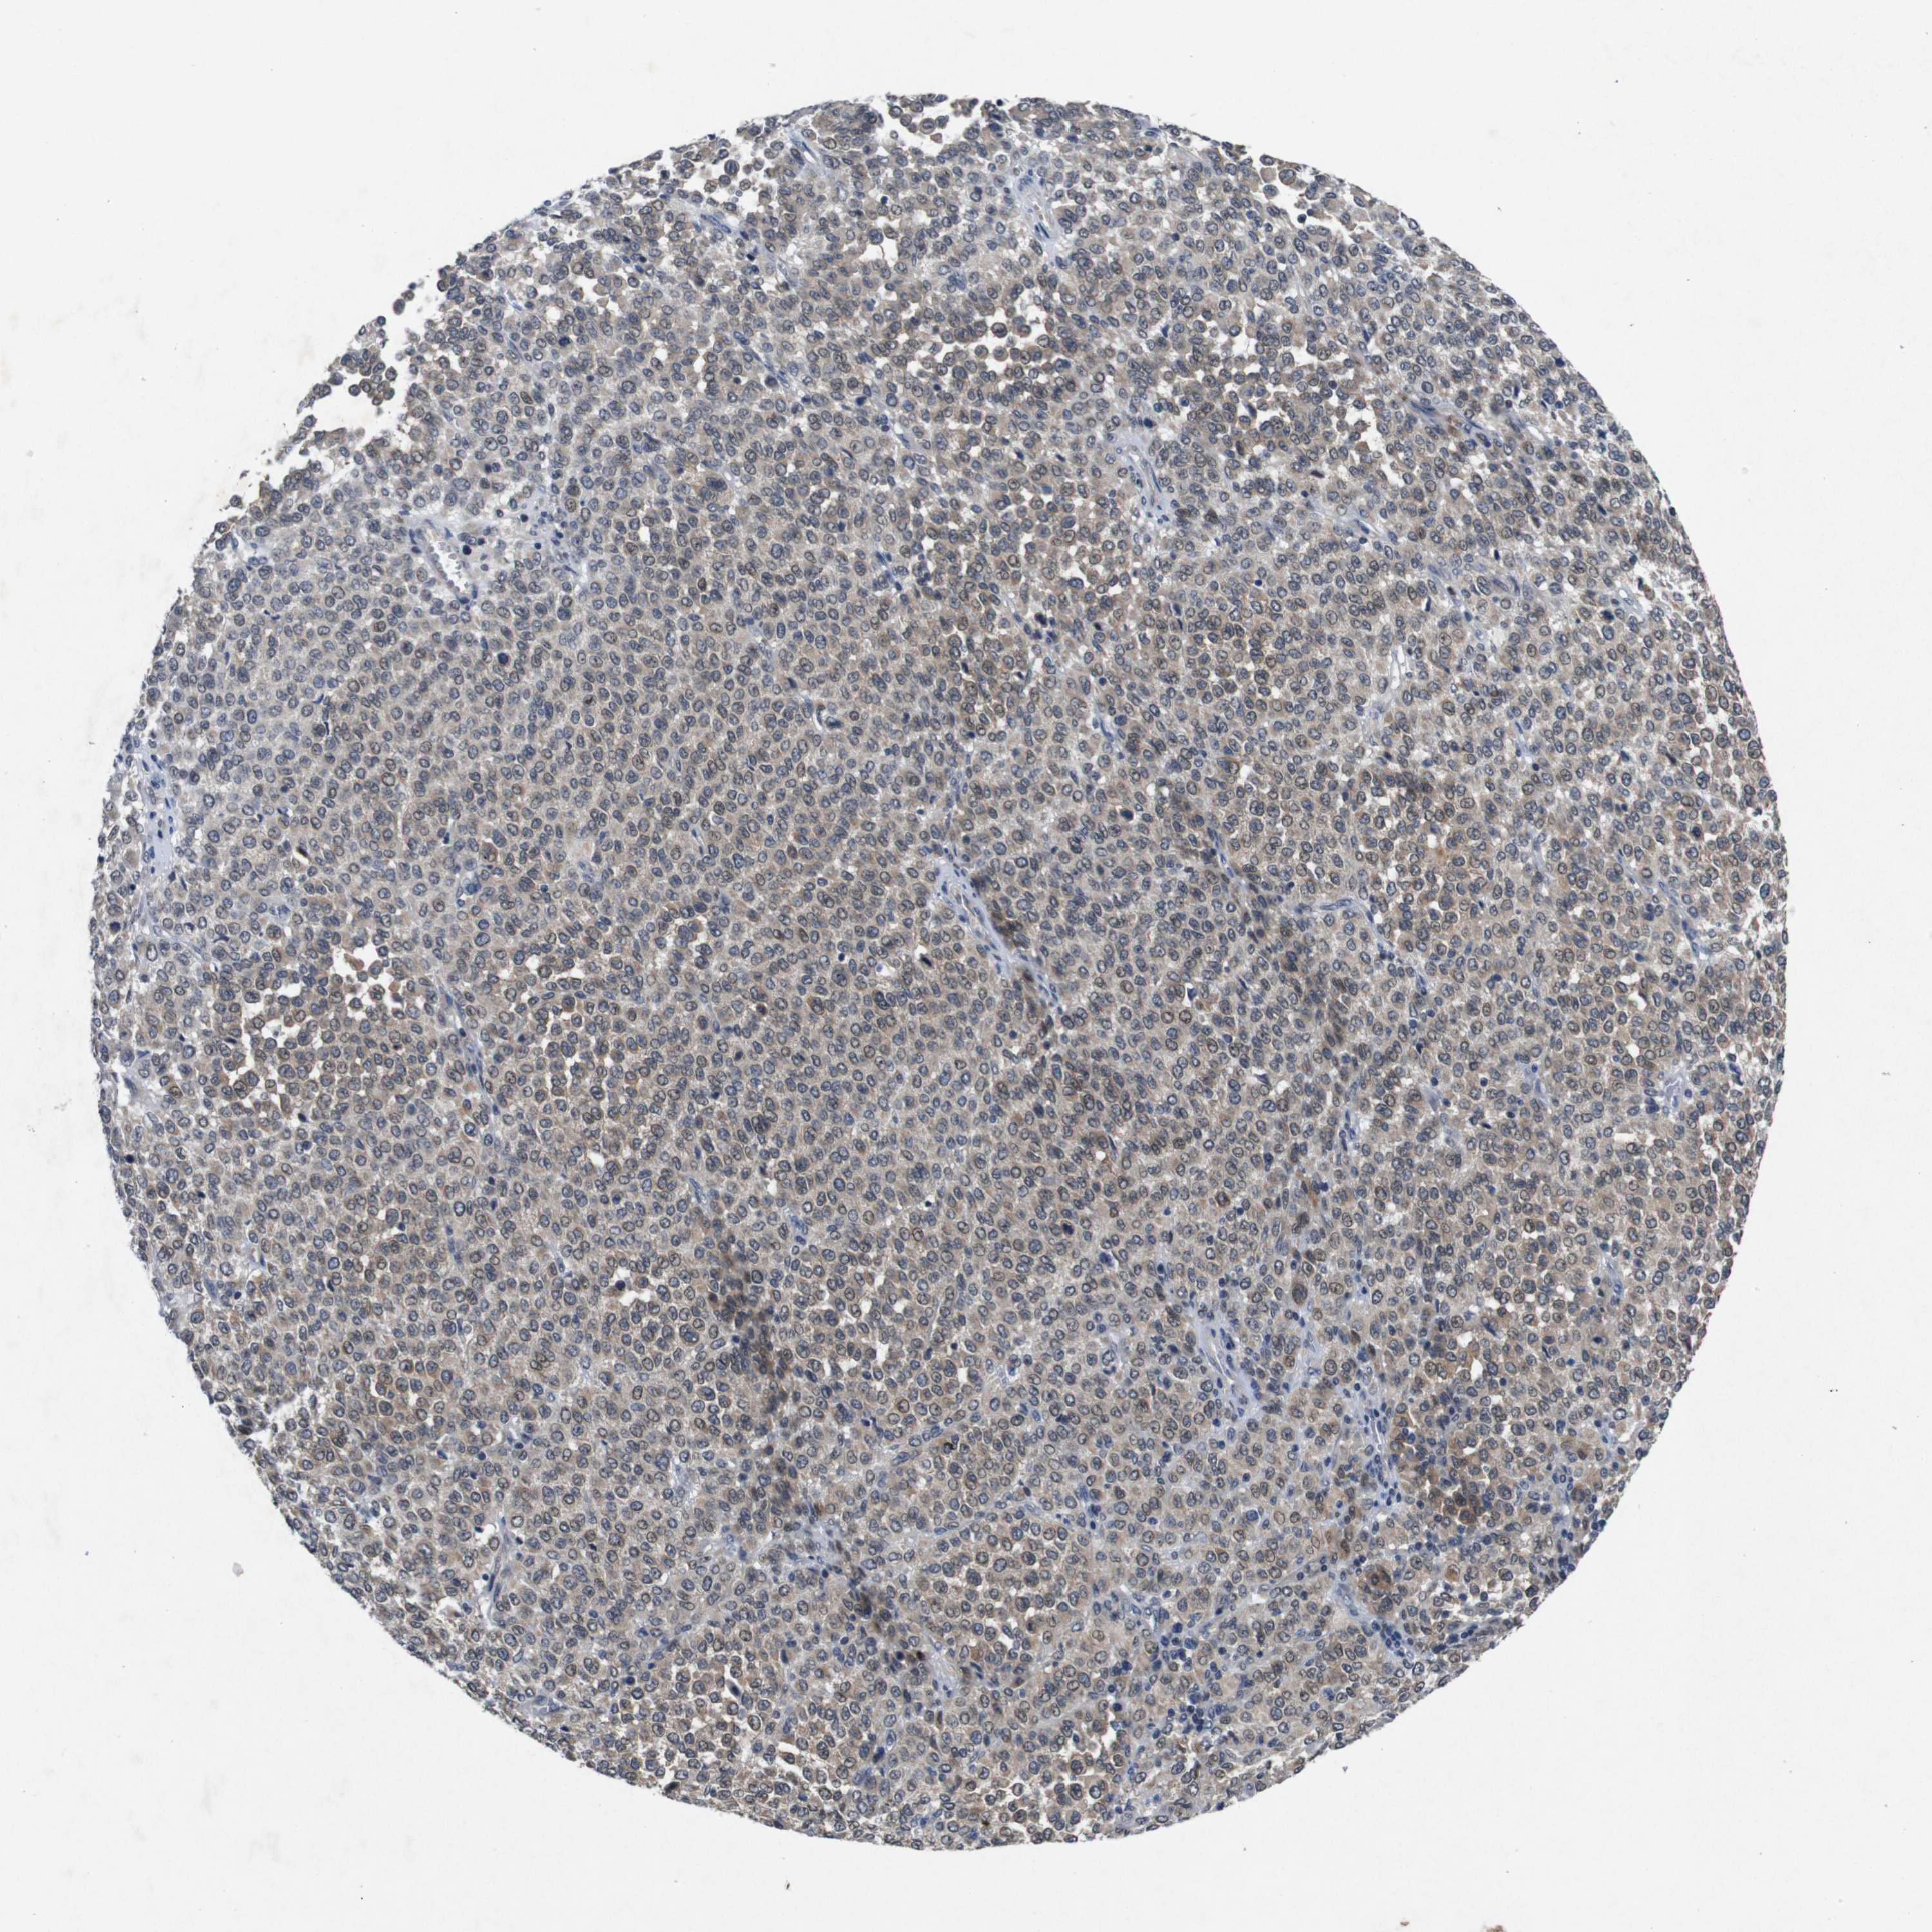

MELANOMA - Protein expressioni

A mouse-over function shows sample information and annotation data. Click on an image to view it in a full screen mode. Samples can be filtered based on level of antibody staining by selecting one or several of the following categories: high, medium, low and not detected. The assay and annotation is described here.

Note that samples used for immunohistochemistry by the Human Protein Atlas do not correspond to samples in the TCGA dataset.

Antibody stainingi

Antibody staining in the annotated cell types in the current human tissue is reported as not detected, low, medium, or high, based on conventional immunohistochemistry profiling in selected tissues. This score is based on the combination of the staining intensity and fraction of stained cells.

Each image is clickable and will lead to virtual microscopy that enables deeper exploration of all samples and also displays staining intensity scores, fraction scores and subcellular localization as well as patient and tissue information for each sample.

Antibody HPA026441

Antibody CAB013090

Staining

High

Medium

Low

Not detected

Intensity

Strong

Moderate

Weak

Negative

Quantity

>75%

75%-25%

<25%

None

Location

Nuclear

Cytoplasmic/membranous

Cytoplasmic/membranous,nuclear

Malignant melanoma, NOS

Malignant melanoma, Metastatic site